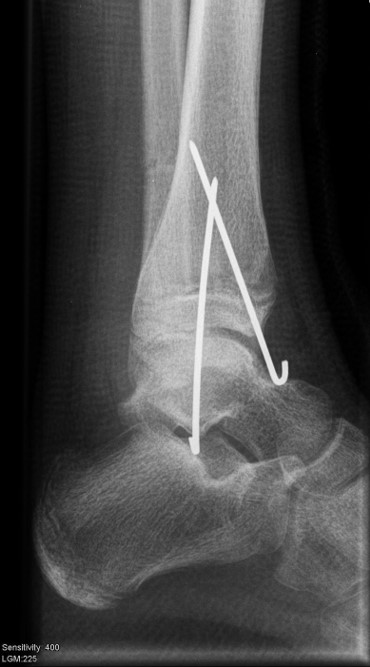

THERAPIE

Behandlungsziel ist die exakte Rekonstruktion der Gelenkfläche sowie die Minimierung des Risikos einer späteren Wachstumsstörung. Dislozierte Frakturen werden offen reponiert, die Osteosynthese erfolgt mit einer Kleinfragmentschraube. Finden sich viele kleine Fragmente kann eine K-Draht Osteosynthese durchgeführt werden. Wird der Innenknöchel operiert, kann bei gleichzeitiger hochgradiger lateraler Instabilität eine Rekonstruktion des lateralen Bandapparats durchgeführt werden. Fibula Frakturen stellen sich meist spontan ein, sodass hier keine zusätzliche Osteosynthese notwendig ist.

Nach der Osteosynthese wird die Fraktur für ca. vier Wochen in einem Unterschenkelgips ruhiggestellt. Bei Schmerzfreiheit der Frakturzone erfolgt anschließend eine schmerzadaptierte Belastungssteigerung über weitere zwei Wochen. Sobald unter Alltagsbedingungen Beschwerdefreiheit besteht kann die sportliche Belastung langsam gesteigert werden. Kirschnerdrähte werden 6-8 Wochen postoperativ, Schrauben nach zwölf Wochen entfernt. Es empfiehlt sich klinische und radiologische Kontrollen im Abstand von 6 Monaten bis zum Wachstumsabschluss durchzuführen, um ein mögliches Fehlwachstum frühzeitig zu erkennen.

Die häufig nicht dislozierten knöchernen Ausrisse können konservativ behandelt werden. Dislozierte Fragmente sollten operativ mit Kirschner-Drähten oder Schrauben fixiert werden (Abb. 32). Die Nachbehandlung umfasst eine 4-wöchige Entlastung im US-Gips. Eine Röntgenkontrolle erfolgt nach Gipsabnahme. Freies Gehen sollte nach 6 Wochen möglich sein. Danach ist auch eine sportliche Belastung des Sprunggelenks möglich (v. Laer 2013).

Eingebrachtes Osteosynthesematerial sollte vor der Vollbelastung entfernt werden.